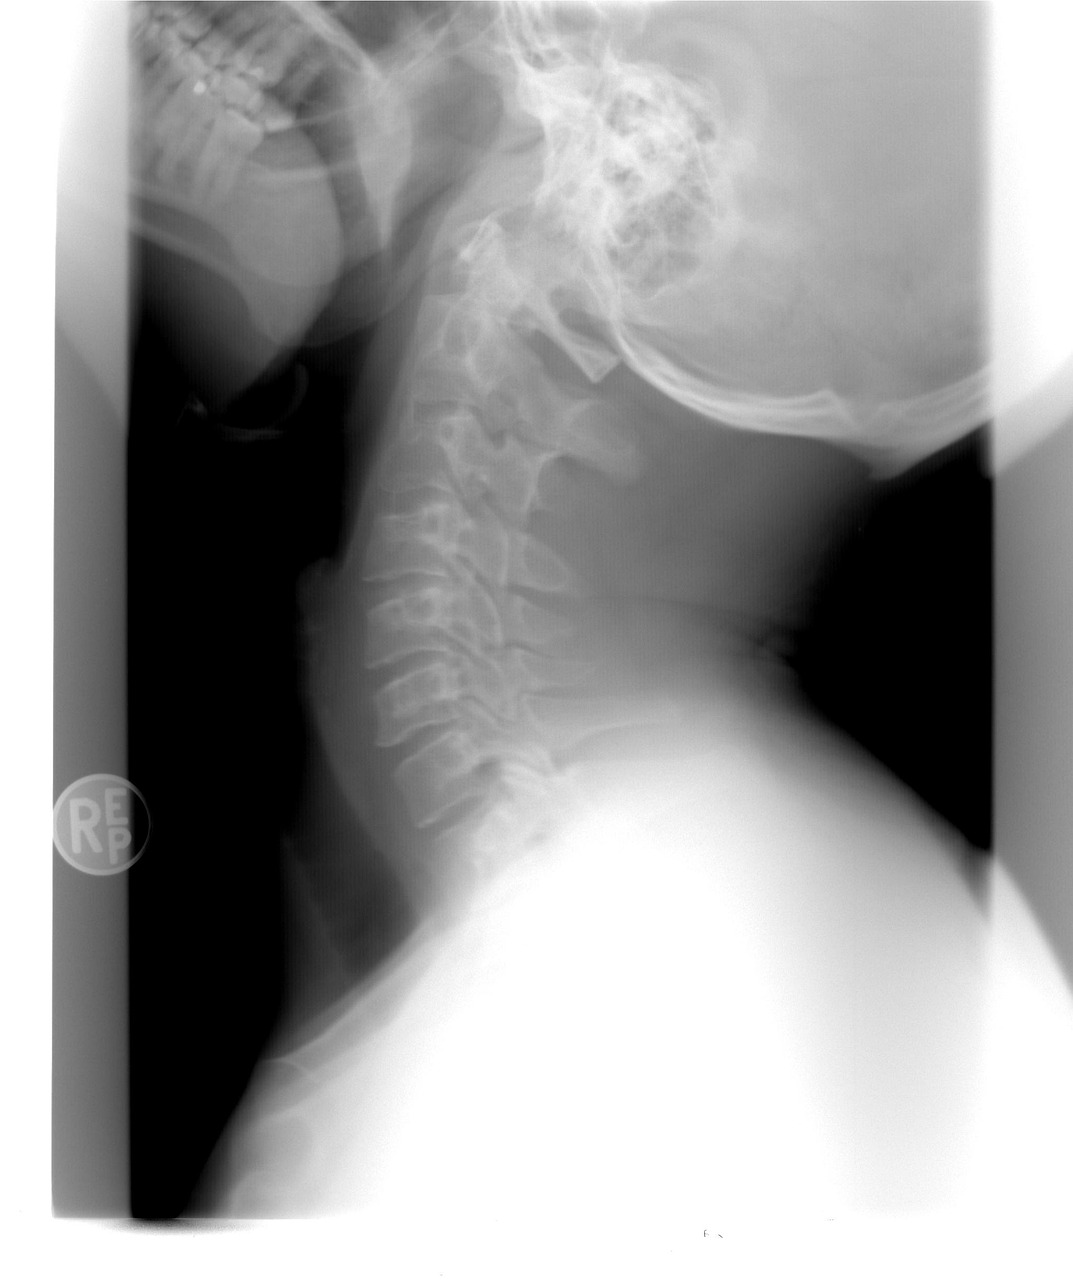

L’avis médical et les imageries permettent de voir l’intégrité des tissus et d’adapter la prise en charge au mieux.

La radiographie permet de voir les tissus durs, l’IRM les tissus mous et durs, l’échographie permet de voir les tissus mous.